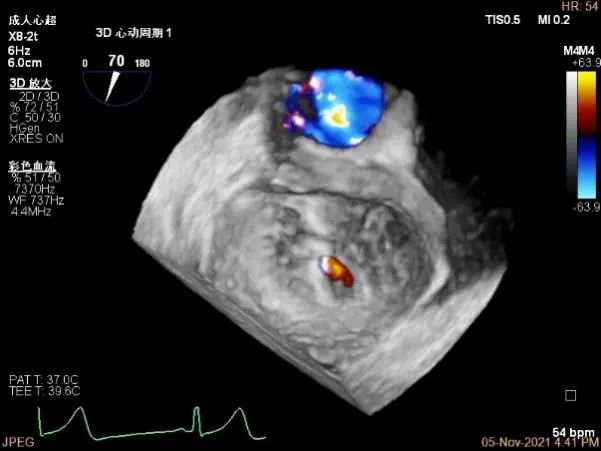

3D-color MV view:血流主要来源于A2区,少部分来源于A1区

Color-view:返流束主要来源于2区脱垂

3D-color:残余少量返流